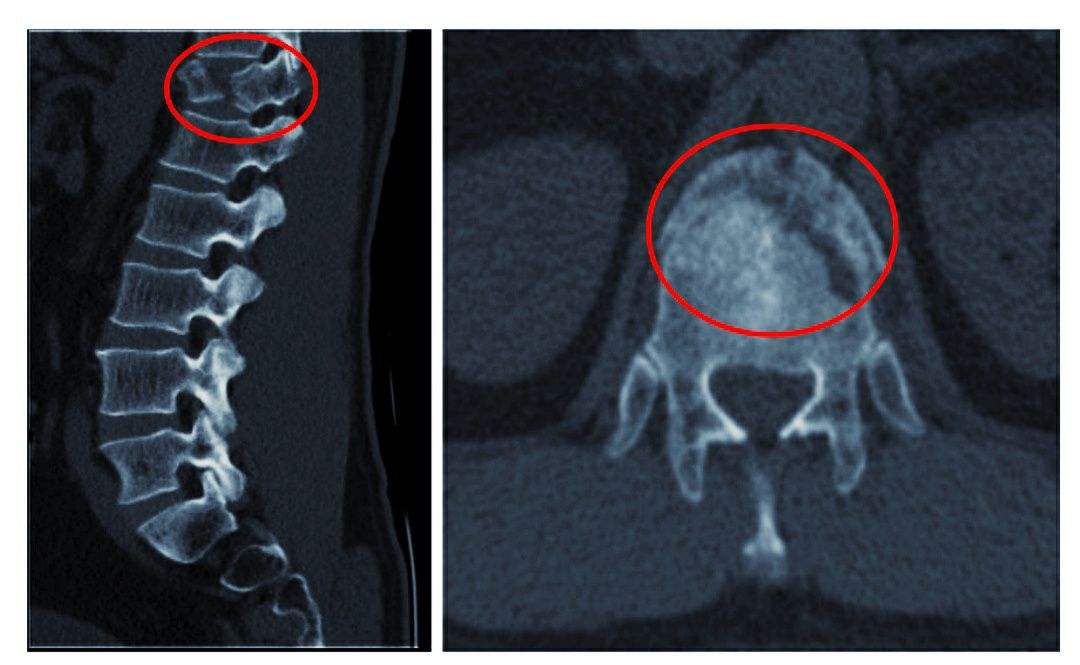

4、脊髓和神經(jīng)根的變化

因脊髓長(zhǎng)期受壓,可出現(xiàn)脊髓變性軟化,甚至出現(xiàn)脊髓空洞,而導(dǎo)致難以恢復(fù)的損傷。其原因主要有血運(yùn)障礙,椎管縱徑縮短,骨贅或椎間盤(pán)組織等混合突出物的直接壓迫脊髓。神經(jīng)根因長(zhǎng)期受壓而發(fā)生變性反應(yīng),出現(xiàn)肢體麻木及運(yùn)動(dòng)障礙。